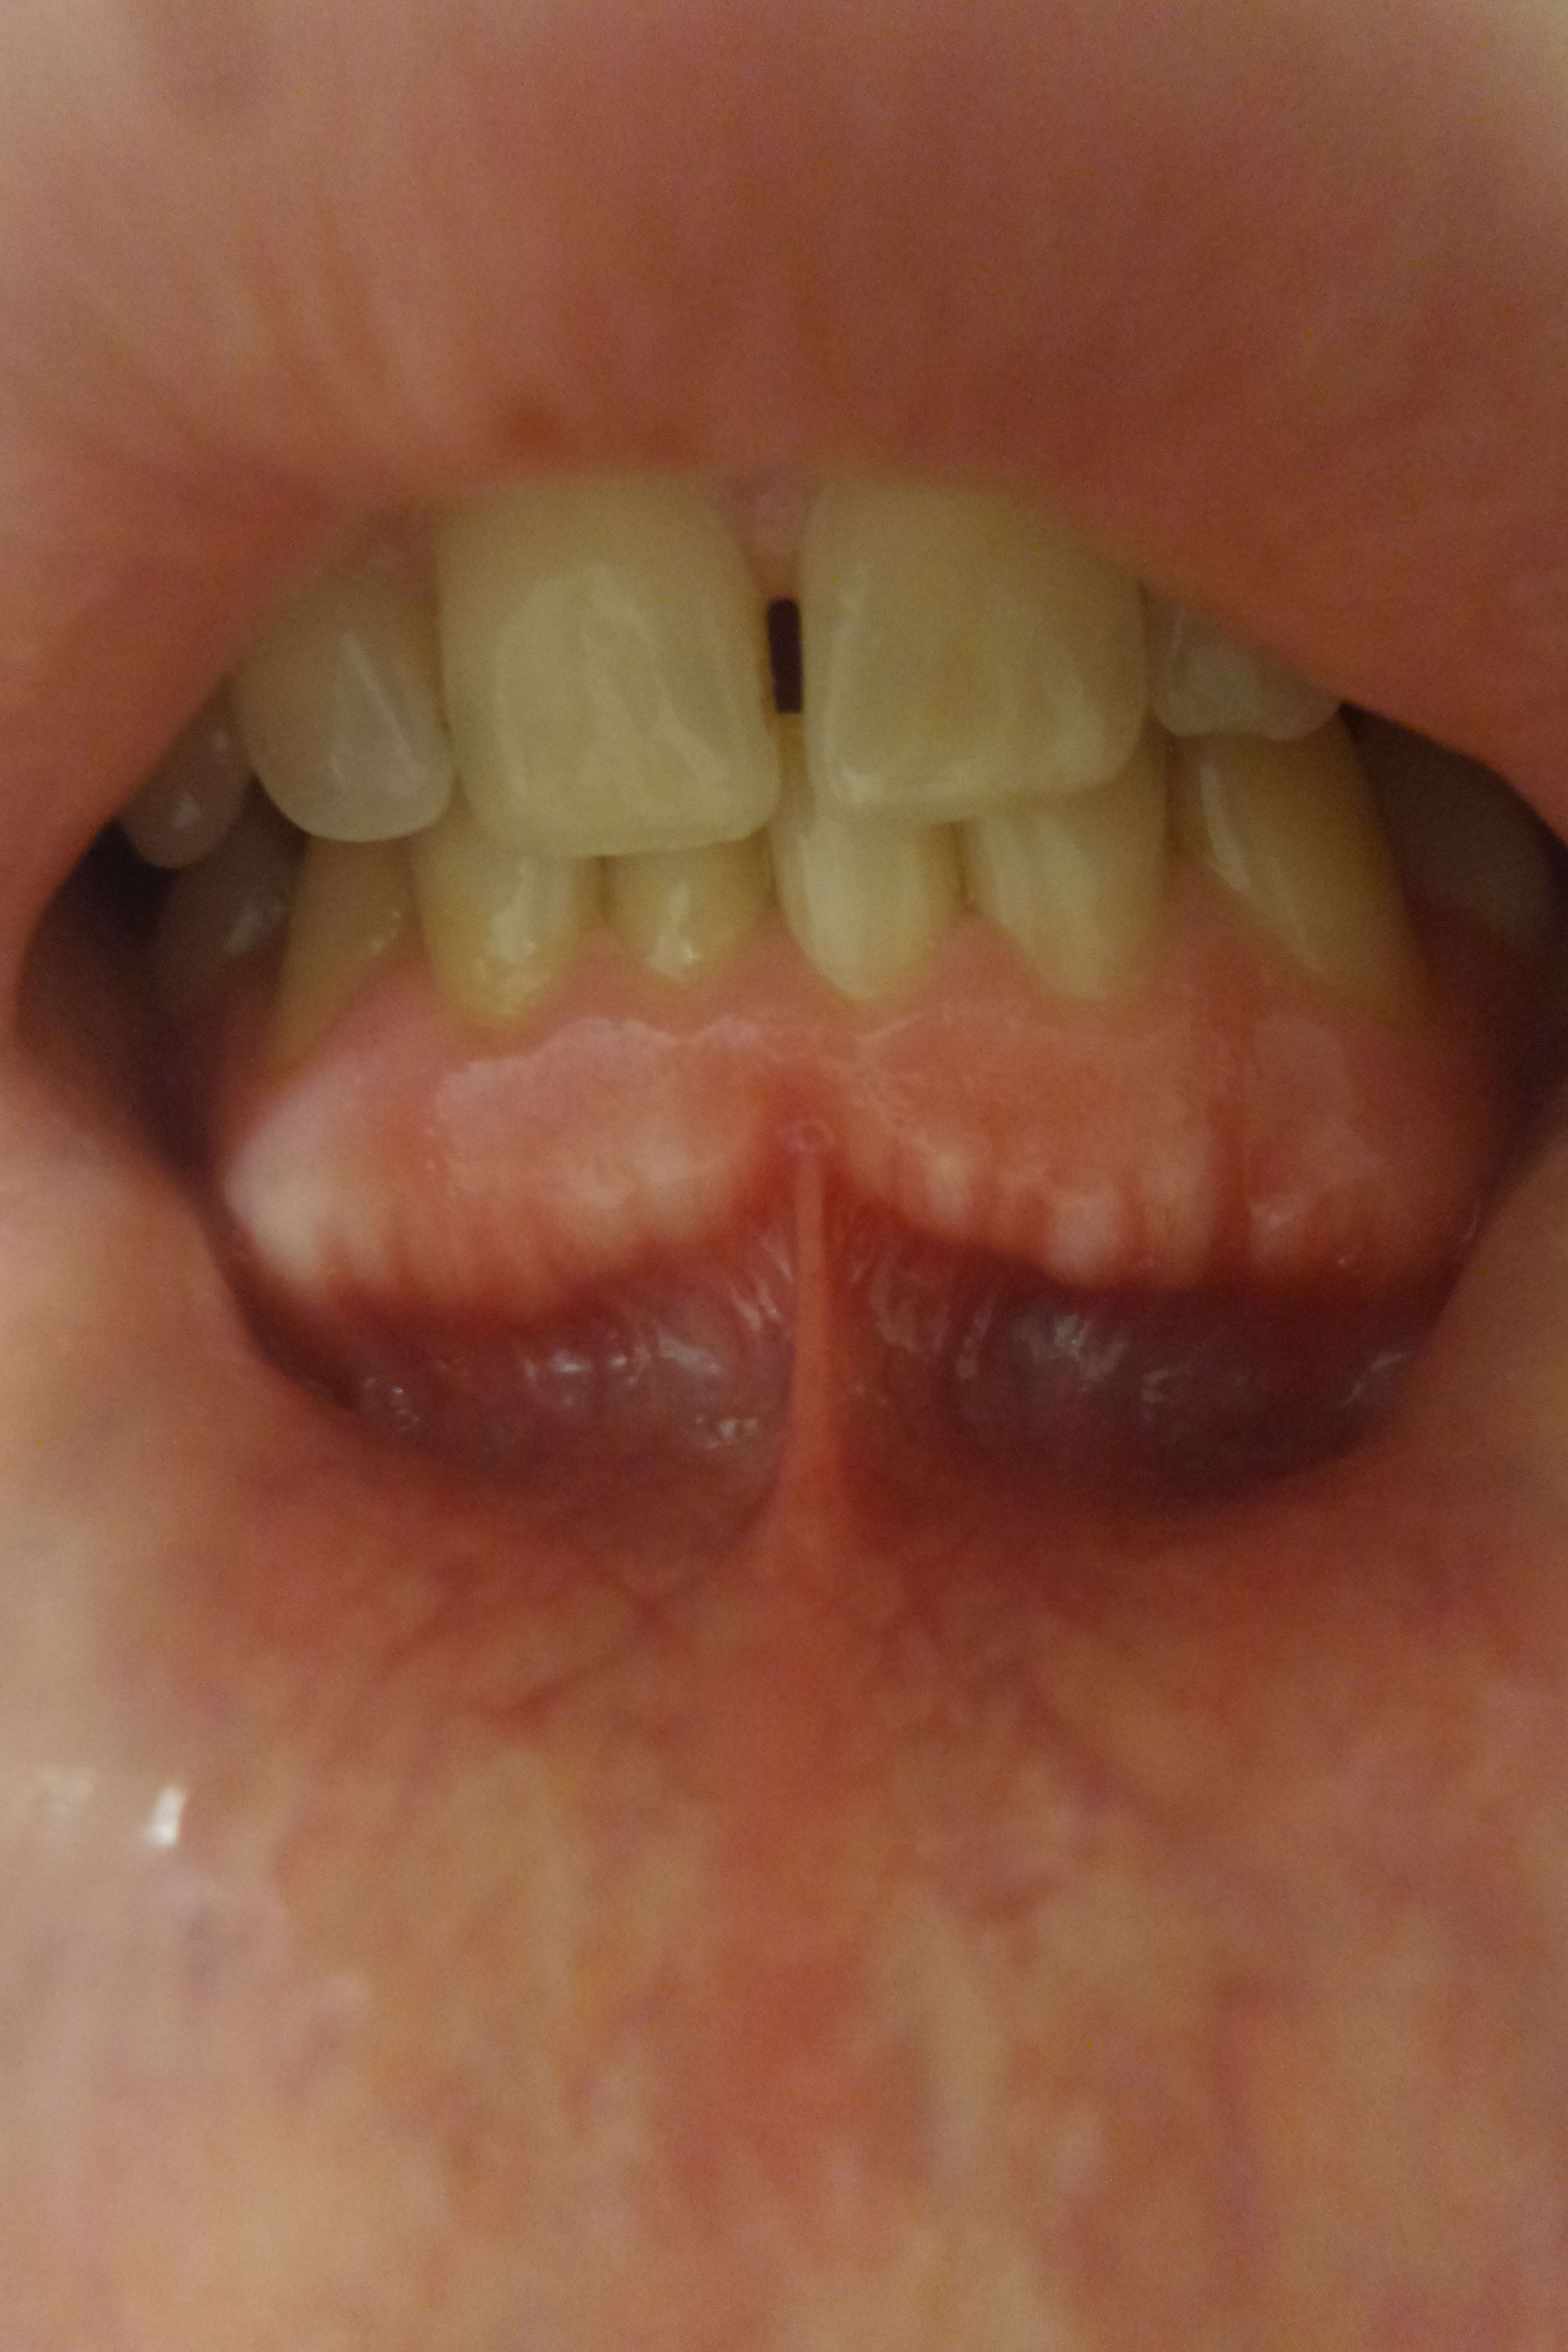

Ce cas présente des tâches blanches au niveau de la gencive inférieure. Il y en avait qu'une il y a 2 ans (celle le plus à droite).